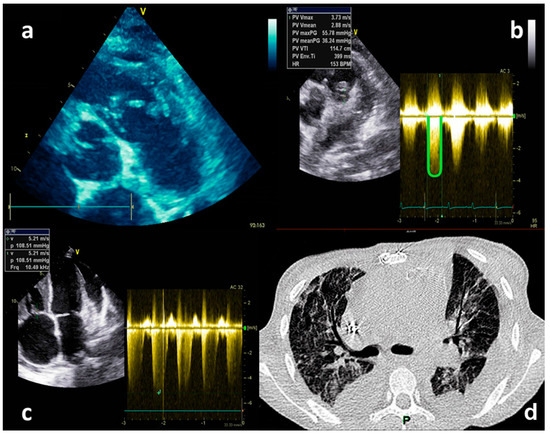

2.2. Case Report No 2